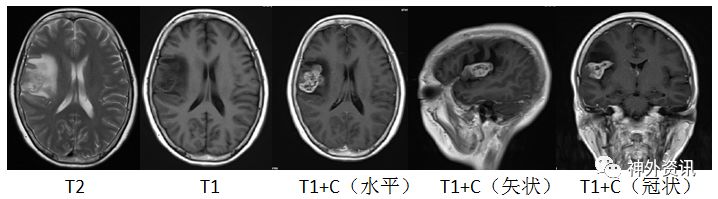

图1.头部MRI增强右侧额叶可见一片状不规则肿块; T1WI上为稍低信号,T2WI上为略高但混杂信号,有不均匀明显强化,约2.8cm×4.3cm×1.9cm。伴有周围水肿。有轻度占位效应。灌注成像:强化肿块区CBF、CBV增高。磁共振波谱:额病灶及周围NAA峰下降,Cho峰升高,伴有脂质乳酸峰出现,提示肿瘤性病变。

术后常规病理报告:(右额颞)胶质母细胞瘤,IDH野生型,WHO IV 级(图5)。

图5. 石蜡切片HE染色,提示胶质母细胞瘤。

免疫组化结果:PTEN +,GFAP +,Ki-67 30%,NF -,NSE +,P53 散在+,MGMT +,Olig2 散在+,ATRX +,BRAF-V600E -,H3K27M -,IDH1 -,S-100 -。